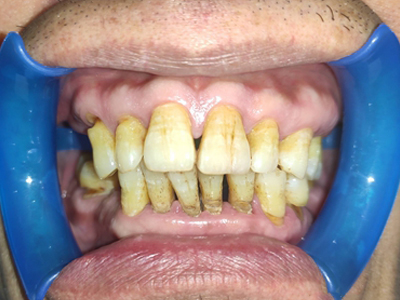

牙龈退缩牙根暴露出现黑斑图

牙龈退缩患者的上排多颗牙齿处的牙龈出现回缩,从而导致牙根外露,外露的牙根上存在黑色的牙菌斑、牙结石,伴有口臭、牙根面敏感等症状。